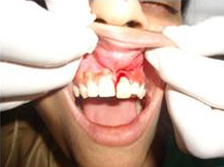

Placement of Bone Grafting

Punch Cut

After Punch Cut